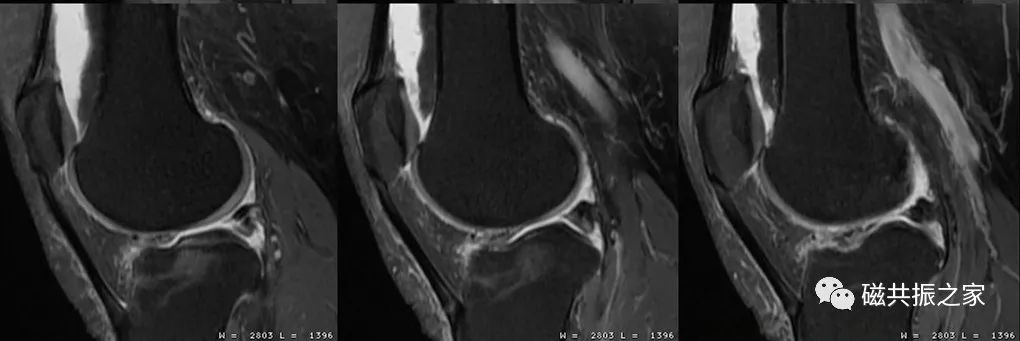

图像的分辨率并不是由单一参数决定的,在调整参数时应综合考虑时间、信噪比、对比度、伪影等相关因素。如图,上1,2,3幅图像的频率编码数为320;下1,2,3幅图像的频率编码数为512;虽然下面三幅图像的扫描体素较上面三幅图像更小,理论上分辨率会更高,但其实际分辨率并不及上面三幅图像。